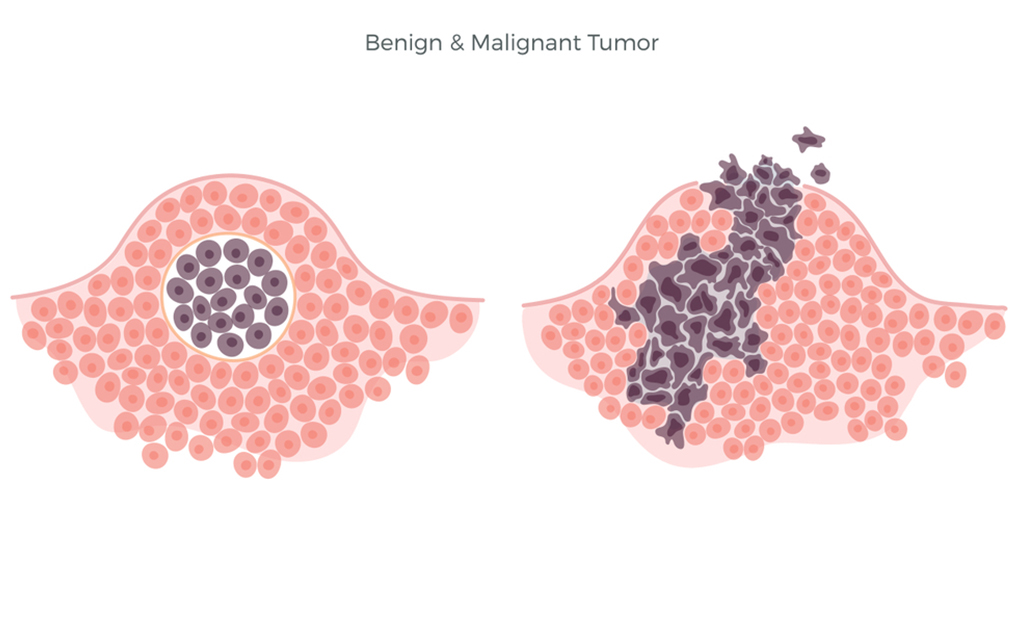

মুখের টিউমার থেকে নিজেকে সুরক্ষিত রাখবেন কীভাবে?

0 SHARES Share Tweet টিস্যুর অস্বাভাবিক বৃদ্ধিকেই সাধারণত টিউমার হিসেবে আখ্যায়িত করা হয়ে থাকে। আর সেটা যদি হয় মুখে বা মু...

ব্রেইন টিউমার | মস্তিষ্কের জটিল এই রোগ সম্পর্কে কতটুকু জানেন?

0 SHARES Share Tweet ব্রেইন টিউমার হলো একটি জটিল শারীরিক অবস্থা, যা ব্রেইনের সেলের অস্বাভাবিক বৃদ্ধির কারণে হয়ে থাকে। এই...